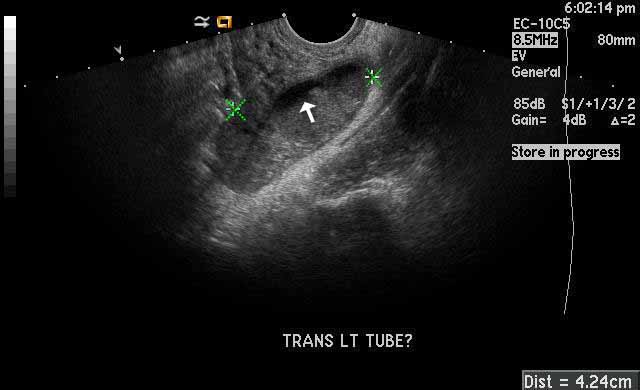

Image 2

Left pyosalpinx. The green calipers mark the dilated fallopian tube filled with anchoic fluid and echogenic pus. The white arrow is pointing towards a fluid-fluid level. |